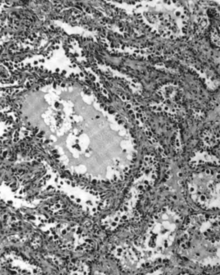

Micrograph of a mucinous ovarian carcinoma stained by H&E. | |

Mucinous adenocarcinoma

Mucinous adenocarcinomas make up 5–10% of epithelial ovarian cancers. Histologically, they are similar to intestinal or cervical adenocarcinomas, and are often actually metastases of appendiceal or colon cancers. Advanced mucinous adenocarcinomas have a poor prognosis, generally worse than serous tumors, and are often resistant to platinum chemotherapy, though they are rare.[18]